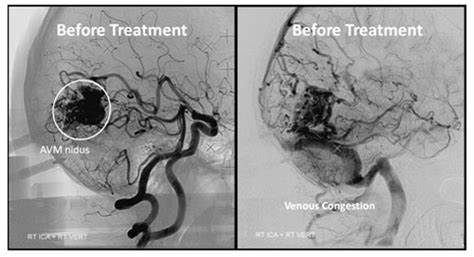

脑动静脉畸形是由异常动脉和静脉网络组成的复杂结构,缺乏中间的毛细血管床,导致血液的高流量动静脉分流。尽管已经描述了家族性病例,但是动静脉畸形是先天性的,并且大多数是偶发的。各种研究报告了与遗传性出血性毛细血管扩张症、斯特奇-韦伯病和威伯恩-梅森综合征等疾病的联系。动静脉畸形常伴有颅内出血,但也可出现癫痫发作、头痛和局灶性神经功能缺损。每年出血风险通常为2%至4%,与5%至25%的死亡风险和10%至50%的神经残疾风险相关。Spetzler-Martin分级系统较初被认为是一种外科风险评估工具,它为AVM大小、位置和静脉引流模式分配分数,通常用于描述临床环境中的动静脉畸形。

血管内的知识应该在全部动静脉畸形的多学科治疗中占有重要地位。除了少数的例外,全部的动静脉畸形都应该用导管脑血管造影来描述,即使保守治疗是可能的。对动脉-静脉血流动力学、供血血管和引流静脉的数量和位置以及相关动脉瘤或静脉流出道梗阻的存在的评估对于适当的决策至关重要。如果选择血管内介入治疗,可能的治疗策略包括手术前栓塞、放射手术前栓塞、治疗性栓塞或姑息性栓塞。